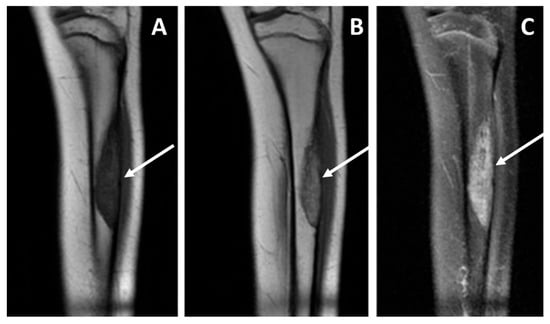

- Internal necrosis (categorized as absent or present [i.e., macroscopic non-enhancing areas after contrast media intravenous injection]).

- Peritumoral edema (categorized as absent, focal [only intraosseous, or only extra-osseous], and diffuse [intra- and extra-osseous]).

- Peritumoral enhancement (categorized as absent, focal, or diffuse).

| Extra-intra osseus extension: Intraosseous only (0), intra- and extra-osseous (1) | Intraosseous only (14), Extra-osseous (2) | Intraosseous only (0), extra-osseous (6) | 0.0004 * |

| Peritumoral edema: absent or focal (0), diffuse intra and extra-osseous (1) | Absent or focal (14), diffuse (2) | Absent or focal (0), diffuse (6) | 0.0004 * |

| Peritumoral enhancement: absent (0), present (1) | Absent (11), Present (1) | Absent (0), present (5) | 0.001 * |